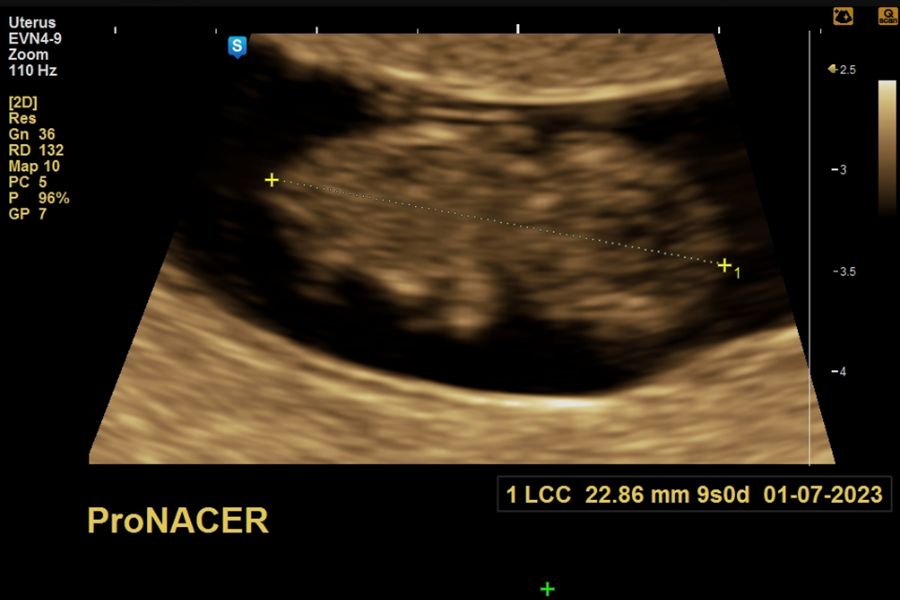

Ecografía de viabilidad desde las 6 a 10 semanas